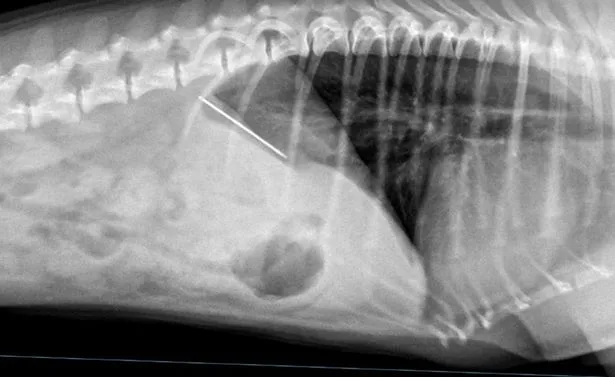

หลังจากนั้น เจ้า Doug ได้ถูกพาส่งโรงพยาบาลสัตว์ Wear Referrals ในเมือง Bradbury มณฑล County Durham และเมื่อทำการเอกซเรย์ก็พบว่าโลหะติดอยู่ในท้องของมันจริงๆ และเจ้าสุนัขตัวน้อยต้องได้รับการรักษาฉุกเฉิน

อย่างไรก็ดี ทีมแพทย์ได้ลองหาวิธีช่วยเอาเข็มและด้ายออกมาโดยที่ไม่ต้องผ่าตัดฉุกเฉิน และแพทญ์ก็เลือกใช้วิธีการรักษา เจ้า Doug ด้วยการส่องกล้องเพื่อเอาเข็มและด้านออกมาได้อย่างปลอดภัยโดยไม่ต้องผ่าตัดใด ๆ และนับจากนั้นเจ้า Doug ก็ค่อยๆฟื้นตัวเต็มที่ จนกระทั่งสามารถกลับบ้านพร้อมเจ้าของได้แล้ว